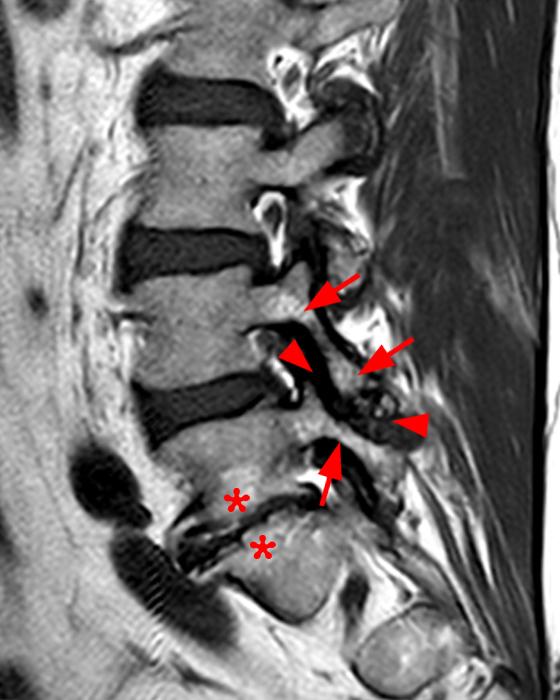

Fig. 14.5, [Severe facet joint arthrosis with...]. Musculoskeletal

Fig. 14.5, [Severe facet joint arthrosis with...]. Musculoskeletal Facet Uncovertebral Joint Arthropathy Facet arthropathy (fa) is a painful, arthritic condition of the facet joints. While facet joints are more critical to the cervical spine’s movements, the uncovertebral joints are also a common location for degeneration and bone spur growth, which can cause many of the same problems as a degenerating facet joint, such as foraminal stenosis. Facet arthrosis is a condition that. Facet Uncovertebral Joint Arthropathy.